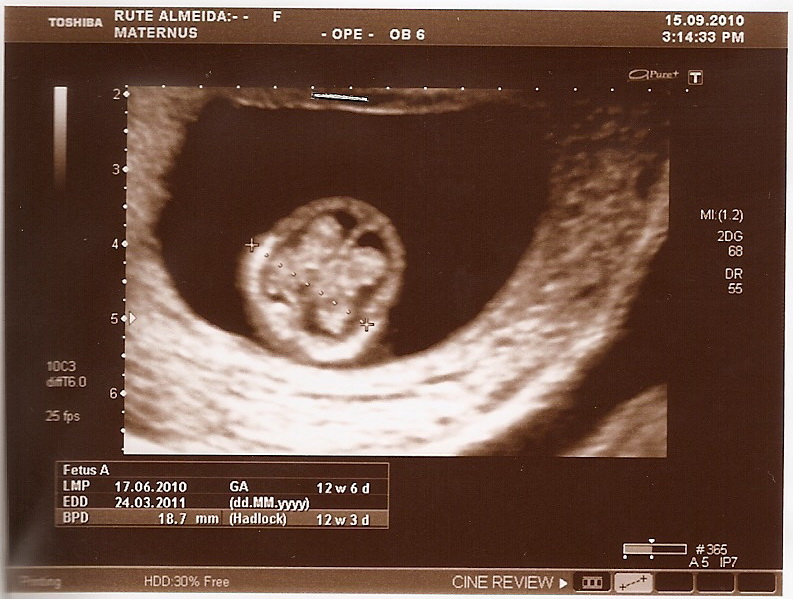

Com 12 semanas de gestação, o bebê chega nos seus 5 a 6 centímetros de comprimento. Por isso neste período, a ecografia obstétrica do 1º trimestre deve ser realizada entre as onze e treze semanas e 6 dias. É através desta ecografia que se pode avaliar toda a anatomia fetal, podendo-se detetar prematuramente algumas malformações.

ECOGRAFIA 12 SEMANA Imagui